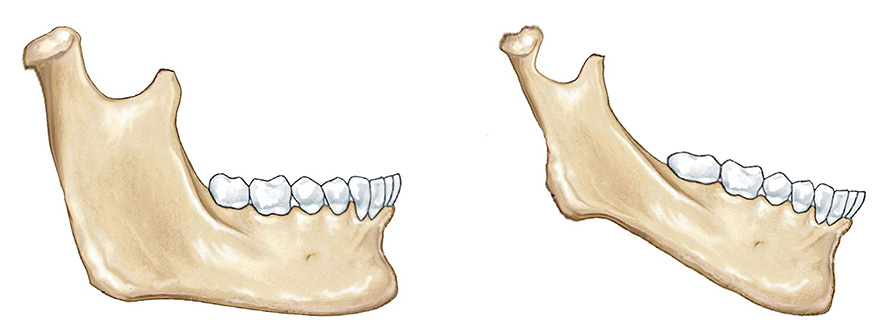

(1)髁状突颈部越粗,说明下颌骨发育越好,越细说明下颌骨发育越差。

(2)下颌骨正中联合越厚,说明下颌骨发育越好,越薄说明下颌骨发育越差。

(3)下颌角前切迹越小,说明下颌骨发育越好,越深说明下颌骨发育越差。

(4)下颌升支越宽,说明下颌骨发育越好,越窄说明下颌骨发育越差。

(5)下颌升支长轴倾斜角度越向下,说明下颌骨发育越好,越向前说明下颌骨发育越差。